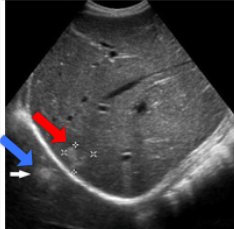

This is a mirror image artifact of what

Hemangioma in the liver